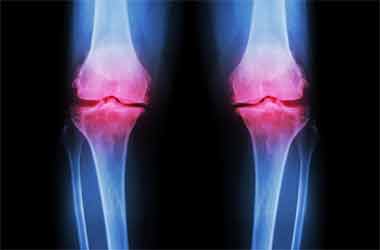

چرا ساییدگی مفصلی در زنها شایعتر است

میدانیم که در سنین

بالا ساییدگی مفصلی و ارتروز در بین زنان شایعتر از مردان است ولی علت آن تا کنون

به درستی شناخته شده نبوده است. اینک مطالعه ای جدید آن را به تفاوت در مواد درون

مایع مفصلی ارتباط داده است.